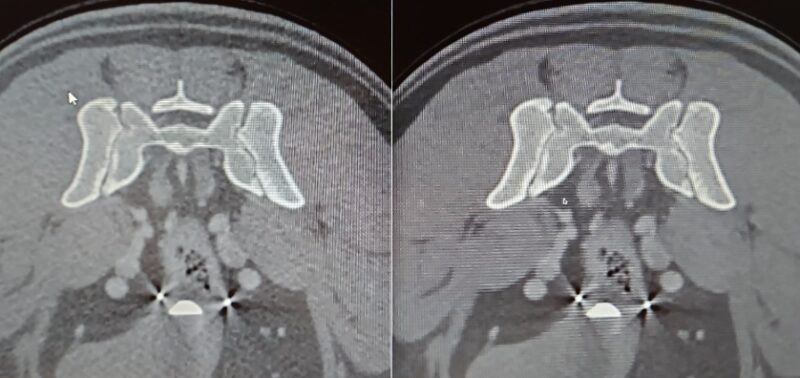

Vergleichende Darstellung eines KI optimierten Kopfscans einer Katze mit einem destruktiven Tumor im Kopfbereich (links original, rechts KI gestützt).